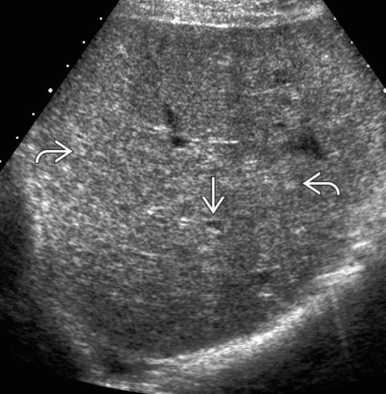

US finding

- 원형으로 경계가 분명한 단순낭종이다.

- 큰 낭종 안에 작은 낭종이 존재(daughter cyst)

- 낭종벽내 석회화가 관찰된다 (cyst wall calcification)

- 백합모양(water-lily sign)

daughter cyst and water-lily sign ②아메바성 간농양 (amoebic abscess)